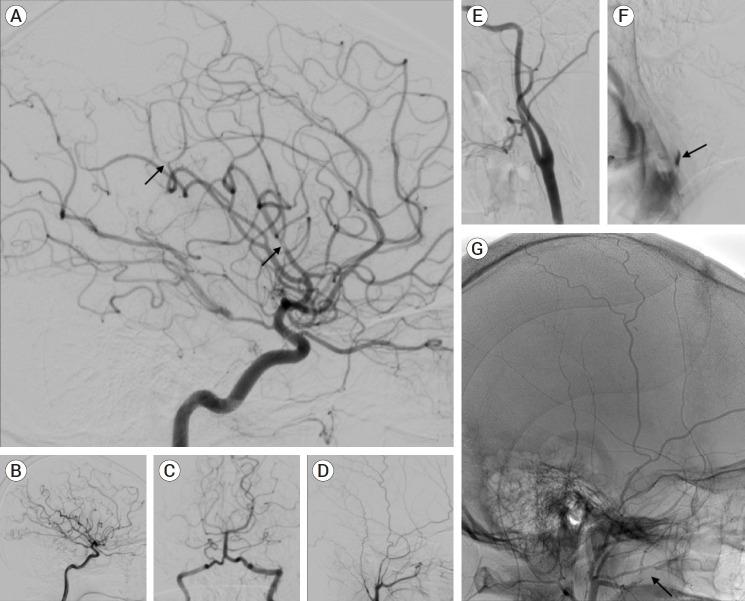

The carotid web (CW), an intimal variant of fibromuscular dysplasia (FMD), is recognized as a cause of stroke and with a high-risk of stroke recurrence. Other names are carotid-bulb atypical FMD, carotid (bulb) diaphragms and it is described like a shelf of tissue from the posterior wall of the carotid bulb. Here we present a case of a young patient with recurrent stroke, with no other risk factors that was diagnosed with a common CW.

颈动脉纤维肌性发育不良内膜变异型(CW)被认为是中风的一个病因,且中风复发风险高。其他名称有颈动脉球部非典型纤维肌性发育不良、颈动脉(球部)隔膜,它被描述为从颈动脉球后壁突出的一层组织。在此,我们报告一例年轻的复发性中风患者,该患者无其他风险因素,被诊断为常见的CW。